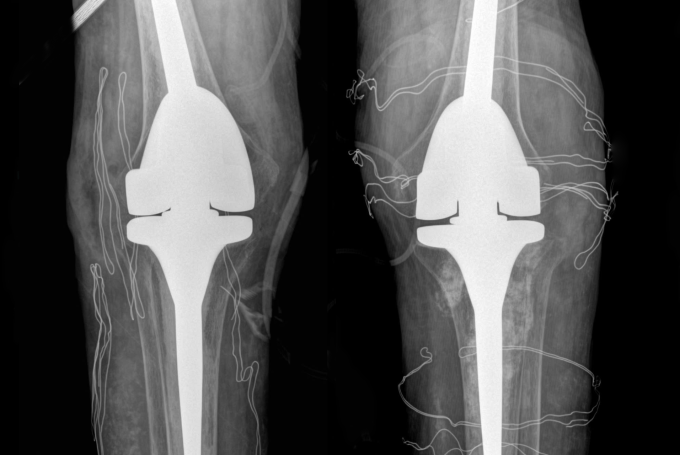

ThS.BS Nguyễn Quang Tôn Quyền, Phó khoa Chấn thương Chỉnh hình, Bệnh viện Đa khoa Tâm Anh Hà Nội, chẩn đoán anh Tiến mất khả năng duỗi khớp gối, chỉ co được 60-70 độ, chụp X-quang cho thấy hai khớp gối bệnh nhân biến dạng nặng, tổn thương tophi khiến khớp và xương tiêu. Kiểm tra loại "thuốc" mua trên mạng mà anh Tiến uống, bác sĩ phát hiện là sản phẩm hỗ trợ sức khỏe đã bị Cục Quản lý Thực phẩm và Dược phẩm Mỹ (FDA) cảnh báo chứa chất dexamethasone gây nguy hiểm.

Anh Tiến được chỉ định phẫu thuật thay khớp nhân tạo. Xét nghiệm máu trước mổ cho thấy nồng độ cortisol và ACTH (hormone kích thích tuyến thượng thận sản xuất cortisol) thấp. Bác sĩ Quyền chẩn đoán bệnh nhân bị suy tuyến thượng thận do lạm dụng chất dexamethasone dài ngày.

Êkíp bác sĩ loại bỏ các hạt tophi gây cản trở vận động, thay thế khớp gối đã tổn thương bằng loại khớp nhân tạo có bản lề, dành riêng cho bệnh nhân có các biến dạng khớp nghiêm trọng. Hậu phẫu, anh Tiến tiếp tục truyền thuốc ổn định nồng độ hormone tuyến thượng thận trong 2 ngày, sau đó duy trì uống thuốc hormone thay thế.